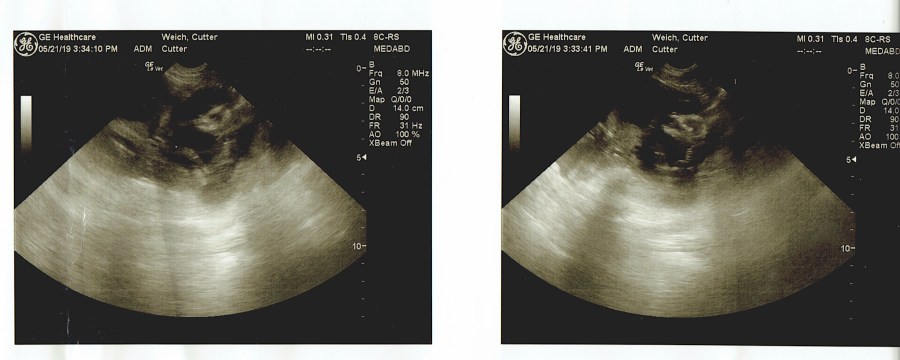

- SUPREME POINT’S TAILING FASTBALL AT WOODECOY JH FITS (CUTTER)